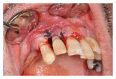

Purpose. Implant therapy plays an important role in contemporary dentistry with high rates of long-term success. However, in recent years, the incidence of peri-implantitis and implant failures has significantly increased. The peripheral giant cell granuloma (PGCG) rarely occurs in peri-implant tissues and it is clinically comparable to the lesions associated with natural teeth. Therefore, the study of possible diseases associated with dental implants plays an important role in order to be able to diagnose and treat these conditions. Materials and Methods. This report described a 60-year-old Caucasian male who presented a reddish-purple pedunculated mass, of about 2 cm in diameter, associated with a dental implant and the adjacent natural tooth. Results. An excisional biopsy was performed and the dental implant was not removed. Histological examination provided the diagnosis of PGCG. After 19-month follow-up, there were no signs of recurrence of peri-implantitis around the implant. Conclusion. The correct diagnosis and appropriate surgical treatment of peri-implant giant cell granuloma are very important for a proper management of the lesion in order to preserve the implant prosthetic rehabilitation and prevent recurrences.